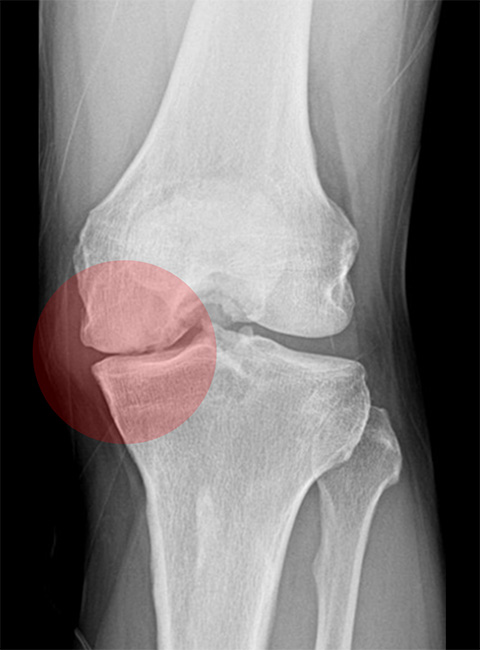

Before

무릎 안쪽 연골 간격이 좁아져 통증을 유발하는 상태

-

After

하중을 무릎 바깥쪽으로 분산시켜 좁아져 있던 무릎 안쪽 간격이 넓어짐 (금속판 제거 후 삽입한 인공뼈도 완전히 유합된 상태)